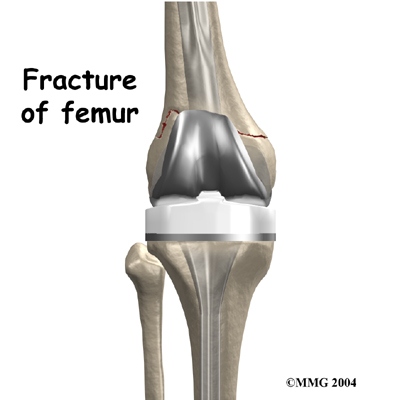

Fracture

Fracture

A fracture may occur near an artificial joint. It is sometimes necessary to use a new artificial joint to fix the fracture. For example, if the where the prosthesis attaches, it may be easier to replace the femoral part of the artificial joint with a new piece that has a longer stem that can hold the fracture together while it heals.

This is similar to fixing the fracture with a metal rod.

Fracture

Fracture